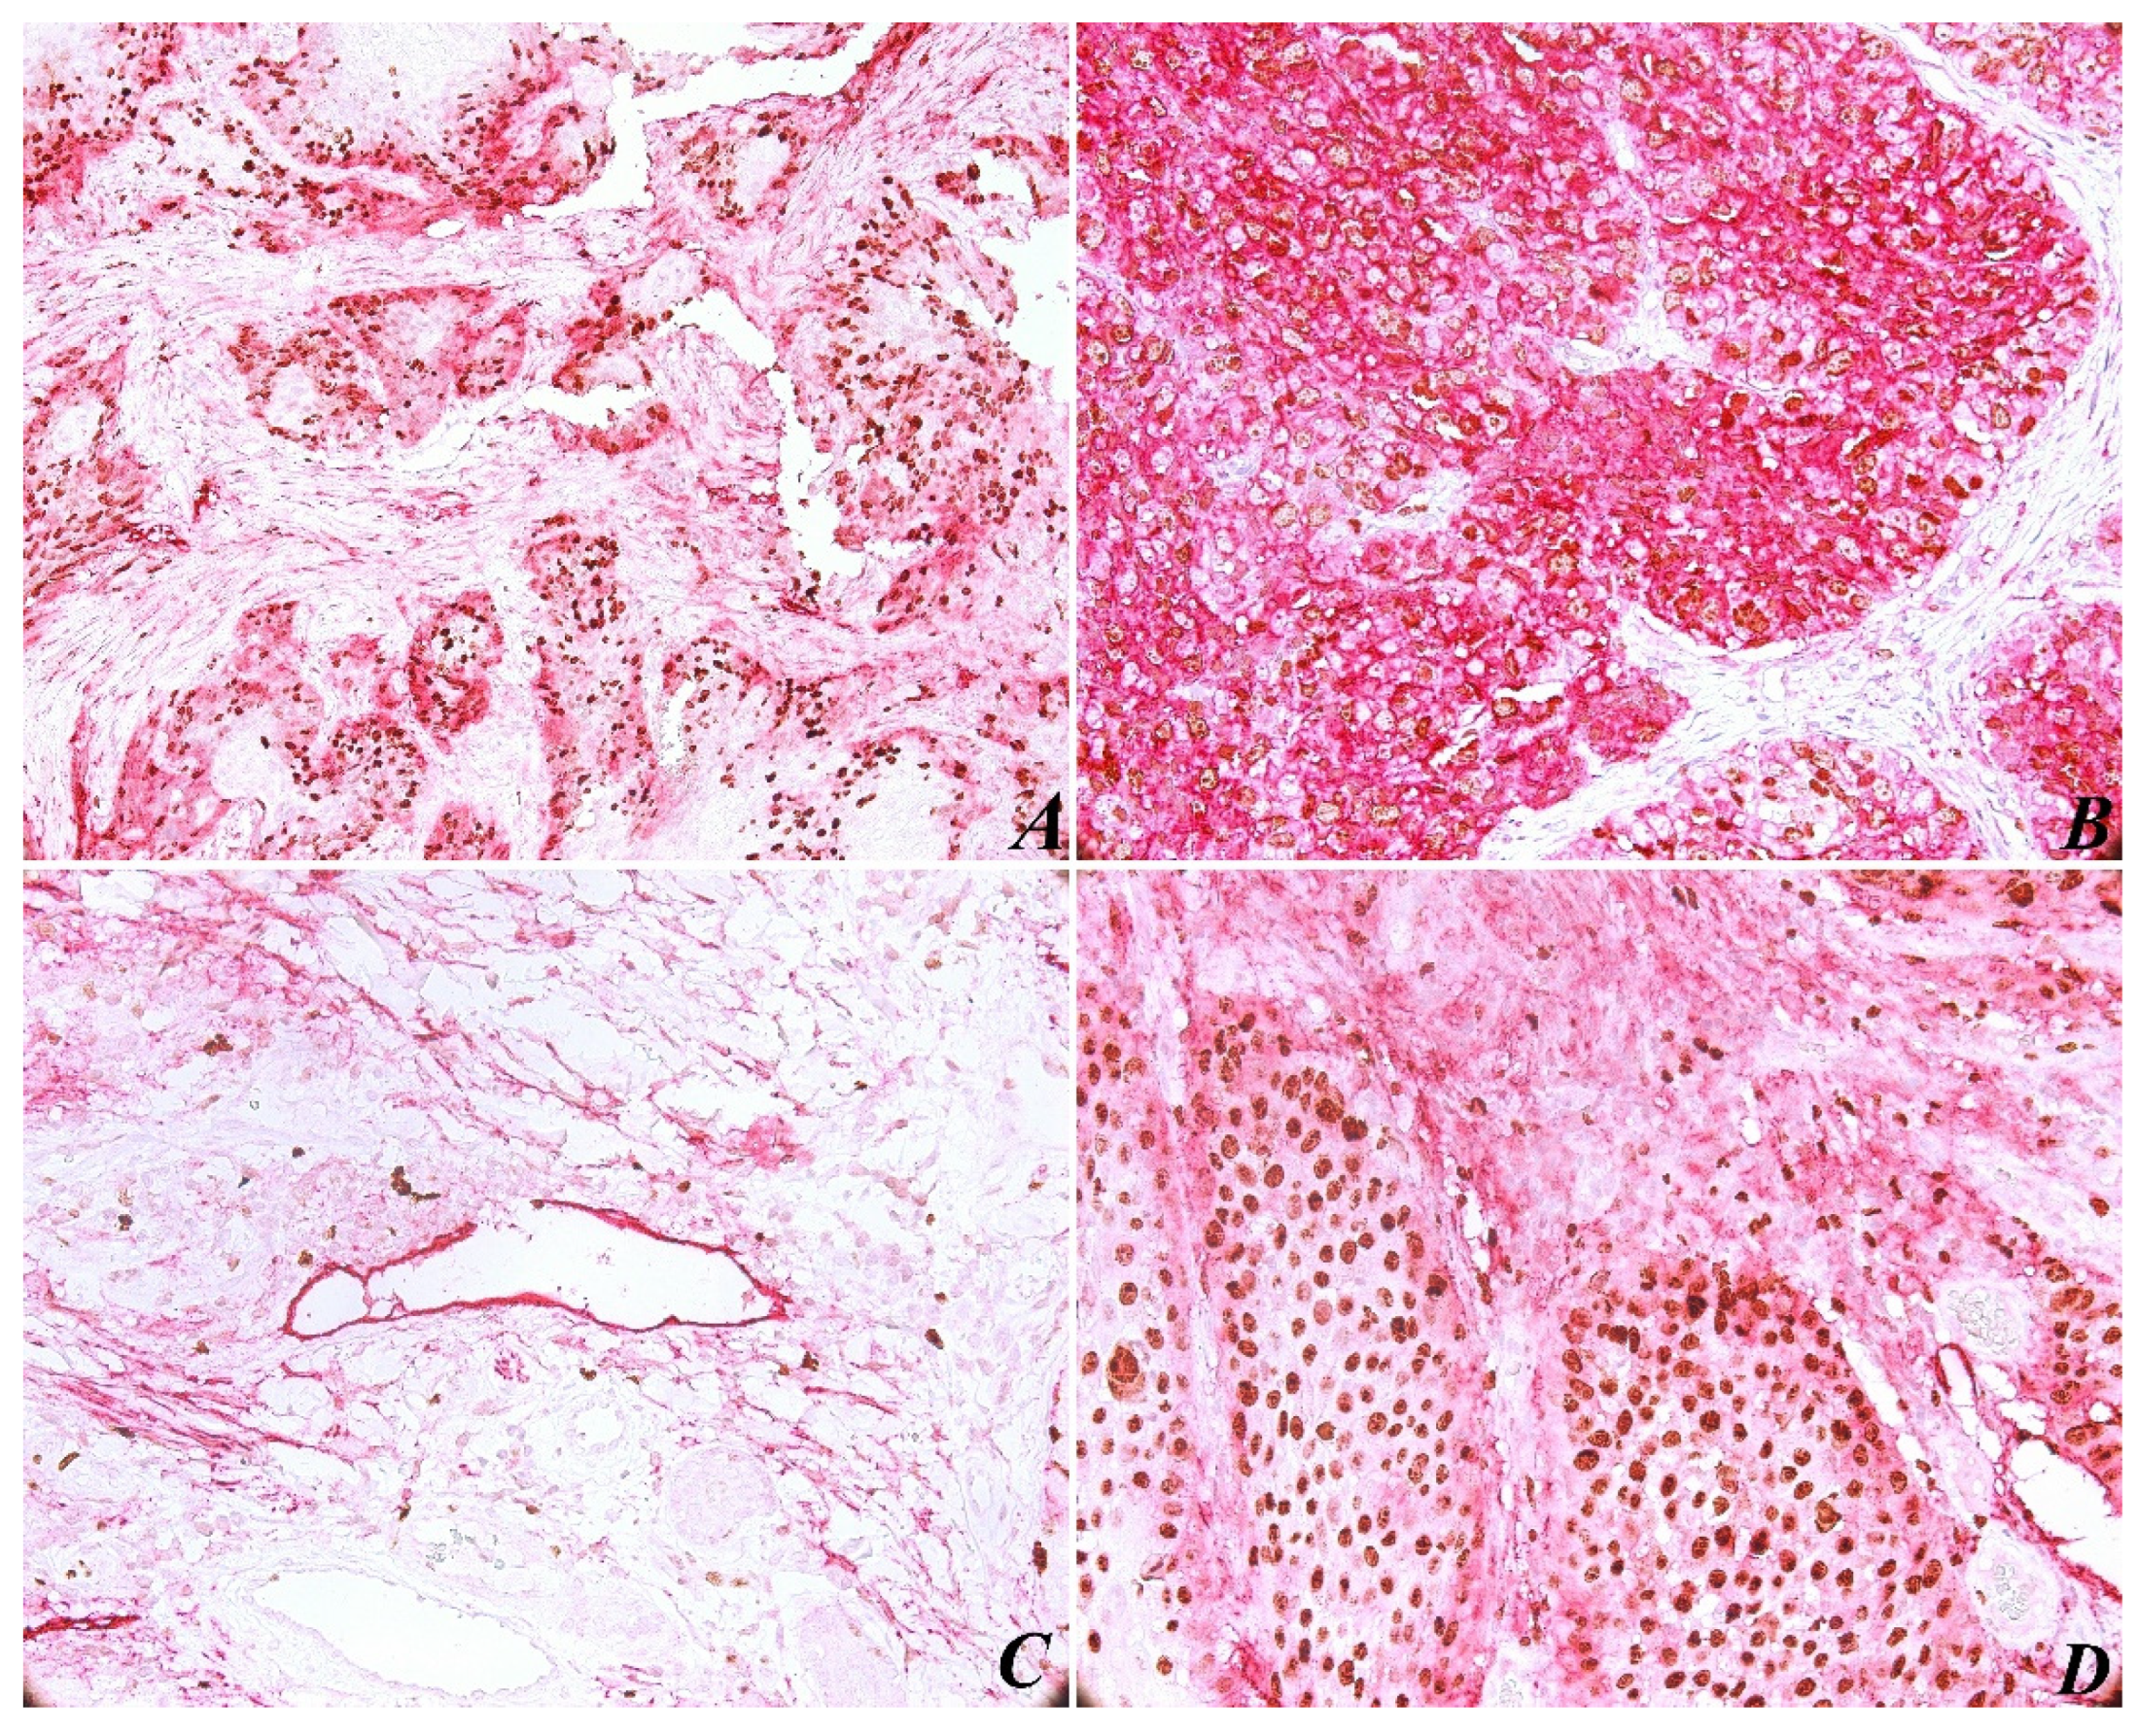

The immunohistochemical evaluation of PDPN expression was identified in almost all cases (with the exception of one case). In most tumors (85%), PDPN was identified in the basal-suprabasal layer of squamous epithelia, with both a cytoplasmic and membranous pattern. As for PDPN immunoexpressing in tumors, high reactivity was present at the periphery of most tumor areas (Figure 1A). As expected, PDPN was highly expressed in cytoplasmic areas of tumor cells (Figure 1B), correlating with high histological grading. The results show a significant correlation between PDPN immunoexpressing and histopathological grading (p < 0.05; p = 0.037) (Table 1).

Figure 1.

Head and neck squamous cell carcinoma specimens stained with the double immunostaining Ki-67 and podoplanin (purple for podoplanin and brownish for Ki67). High reactivity of podoplanin was present at the periphery of tumor areas, score +2, original magnification ×200 (A). Height expression of podoplanin score +3 and Ki-67 score +3 in tumor area, original magnification ×200 (B). Peritumoral lymphatic vessel with endothelial wall disrupted by tumor cell invasion, original magnification ×200 (C). Podoplanin expression at the periphery of tumor and proliferation index Ki-67 score +3, original magnification ×400 (D).

Another observation concerned lymphovascular invasion (LVI), which is defined by the identification in the LV lumen of isolated tumor cells, small groups of tumor cells, or by discontinuous wall of the lymphatic vessels by tumor invasion (Figure 1C). In this case, due to Ki-67/PDPN double staining, we found 15 tissue samples with LVI, counting the entire tumor tissue sample. We found no major differences between peritumoral and intratumoral LVD, no significant correlation between LVI and histological grading (p < 0.05; p = 0.976), and tumor proliferation assessed by Ki-67 expression was not relevant (p < 0.05; p = 0.413). We believe that such a correlation was not possible because the current stage of the tumor evidence did not show loco-regional lymph node metastasis.

The immunohistochemical evaluation of Ki-67 nuclear staining was observed in all 50 cases. An increased Ki-67 proliferation index was present in 82% of tumor areas (Table 4), and a statistical correlation was found between this and histological grading (p < 0.05; p = 0.050). In addition, we recorded a statistically significant correlation between Ki-67 expression and PDPN expression (p < 0.05; p = 0.028). However, an analysis of Ki-67 nuclear labeling and LMVD profile was not significant (p < 0.05; p = 0.896). In the tumor areas, both peripheral and central cells of the tumor islets were positively immunostained with Ki-67 (Figure 1D). Immunoreactivity for Ki-67 was limited to the nucleus in all samples, and PDPN staining was present in different intensities in cytoplasmic tumor cells.